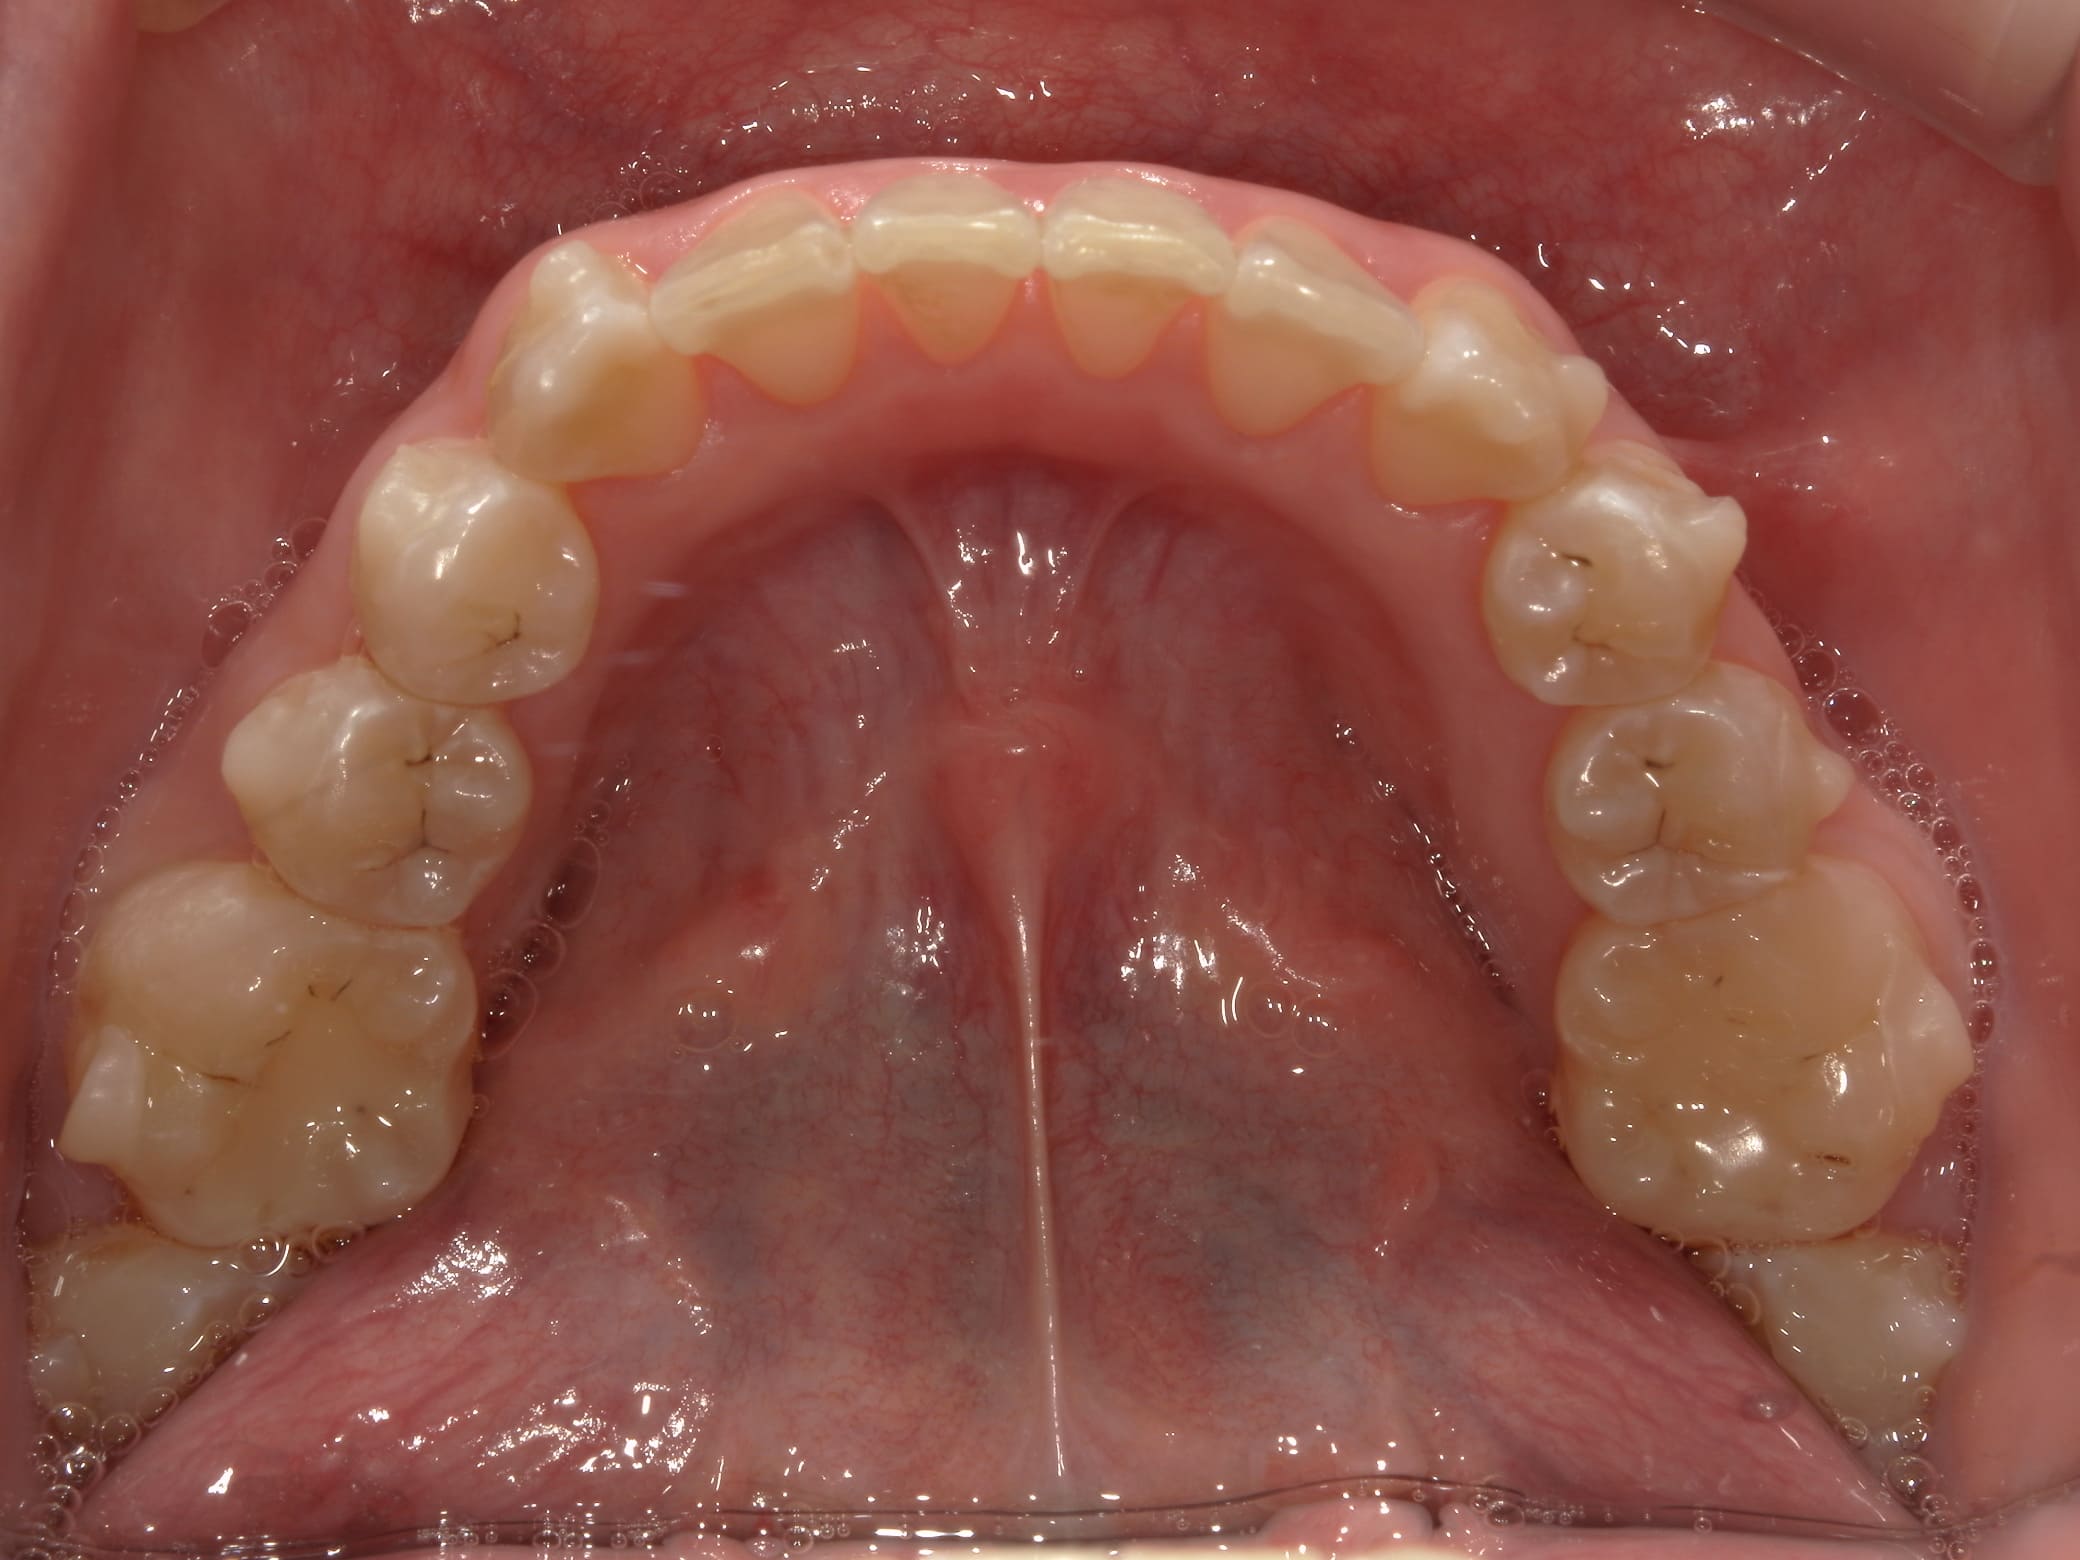

| 年齢・性別 | 21歳 |

|---|---|

| 主訴 | 叢生が気になる・前歯に埋伏歯がある |

| 治療期間・回数 | 6ヶ月 |

| 費用 | 935,000円 |

| 上顎の左側3番が埋伏していたため、上顎左右の3番および親知らずを抜歯し、矯正治療を行いました。 治療開始からおよそ6ヶ月で歯列が整い、審美的にも機能的にも良好な結果が得られた症例です。 |